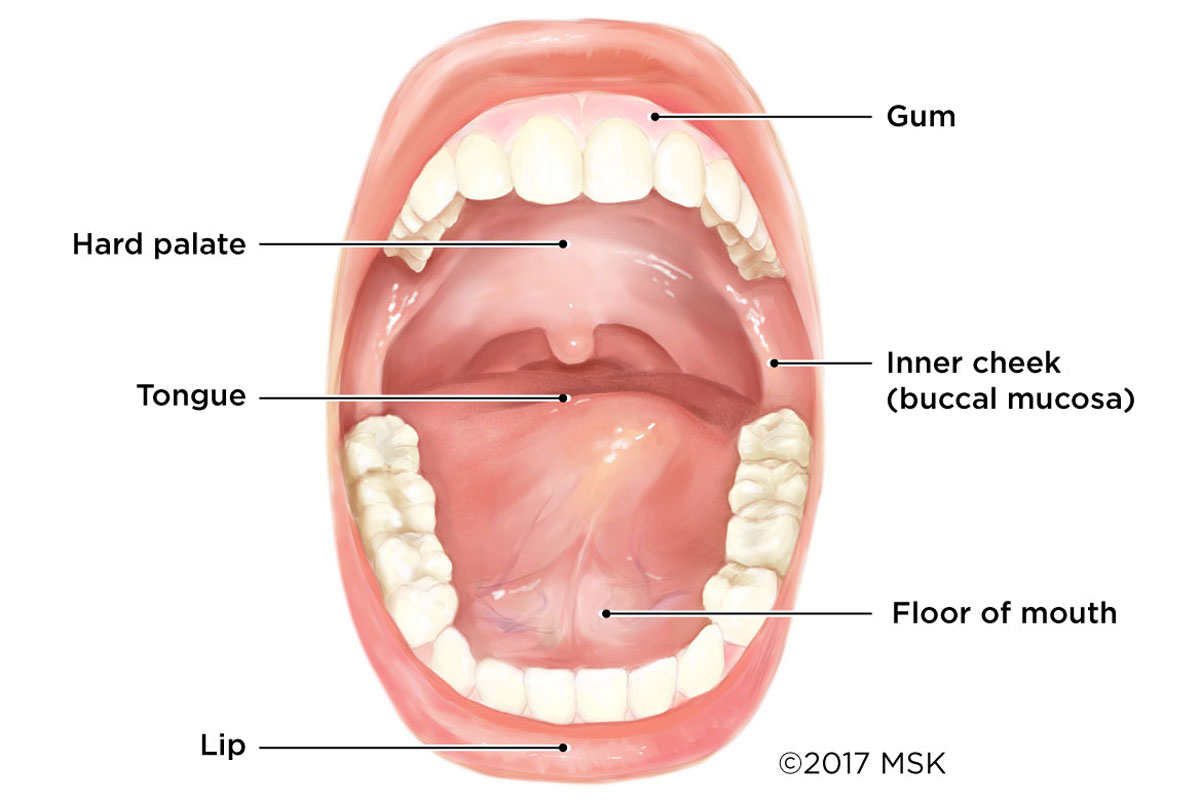

Oral Cancer Mouth Cancer Anatomy Headandneckcancerguide Org

Early Stage Oral Cavity Cancer Memorial Sloan Kettering

Mouth Cancer Memorial Sloan Kettering Cancer Center

Malignant Tumors Of The Floor Of The Mouth Background

Cancers Of The Floor Of The Mouth

Cancers Of The Floor Of The Mouth